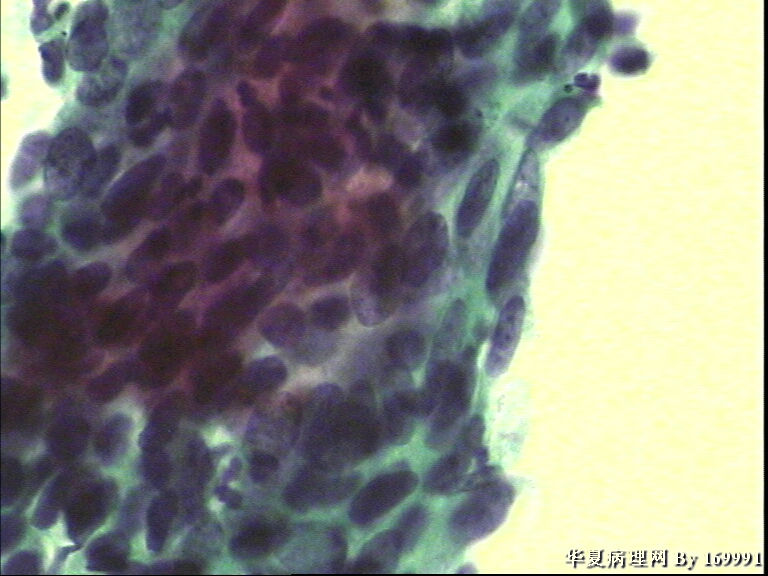

宫颈液基,患者60岁,宫颈轻糜,鳞癌?

• 宫颈液基,患者60岁,宫颈轻糜,鳞癌?图1

图1

是的,此例没有直接报癌,最后报了HSIL,不除外SCC.建议活检。

宫颈活检结果:宫颈原位癌,累腺。